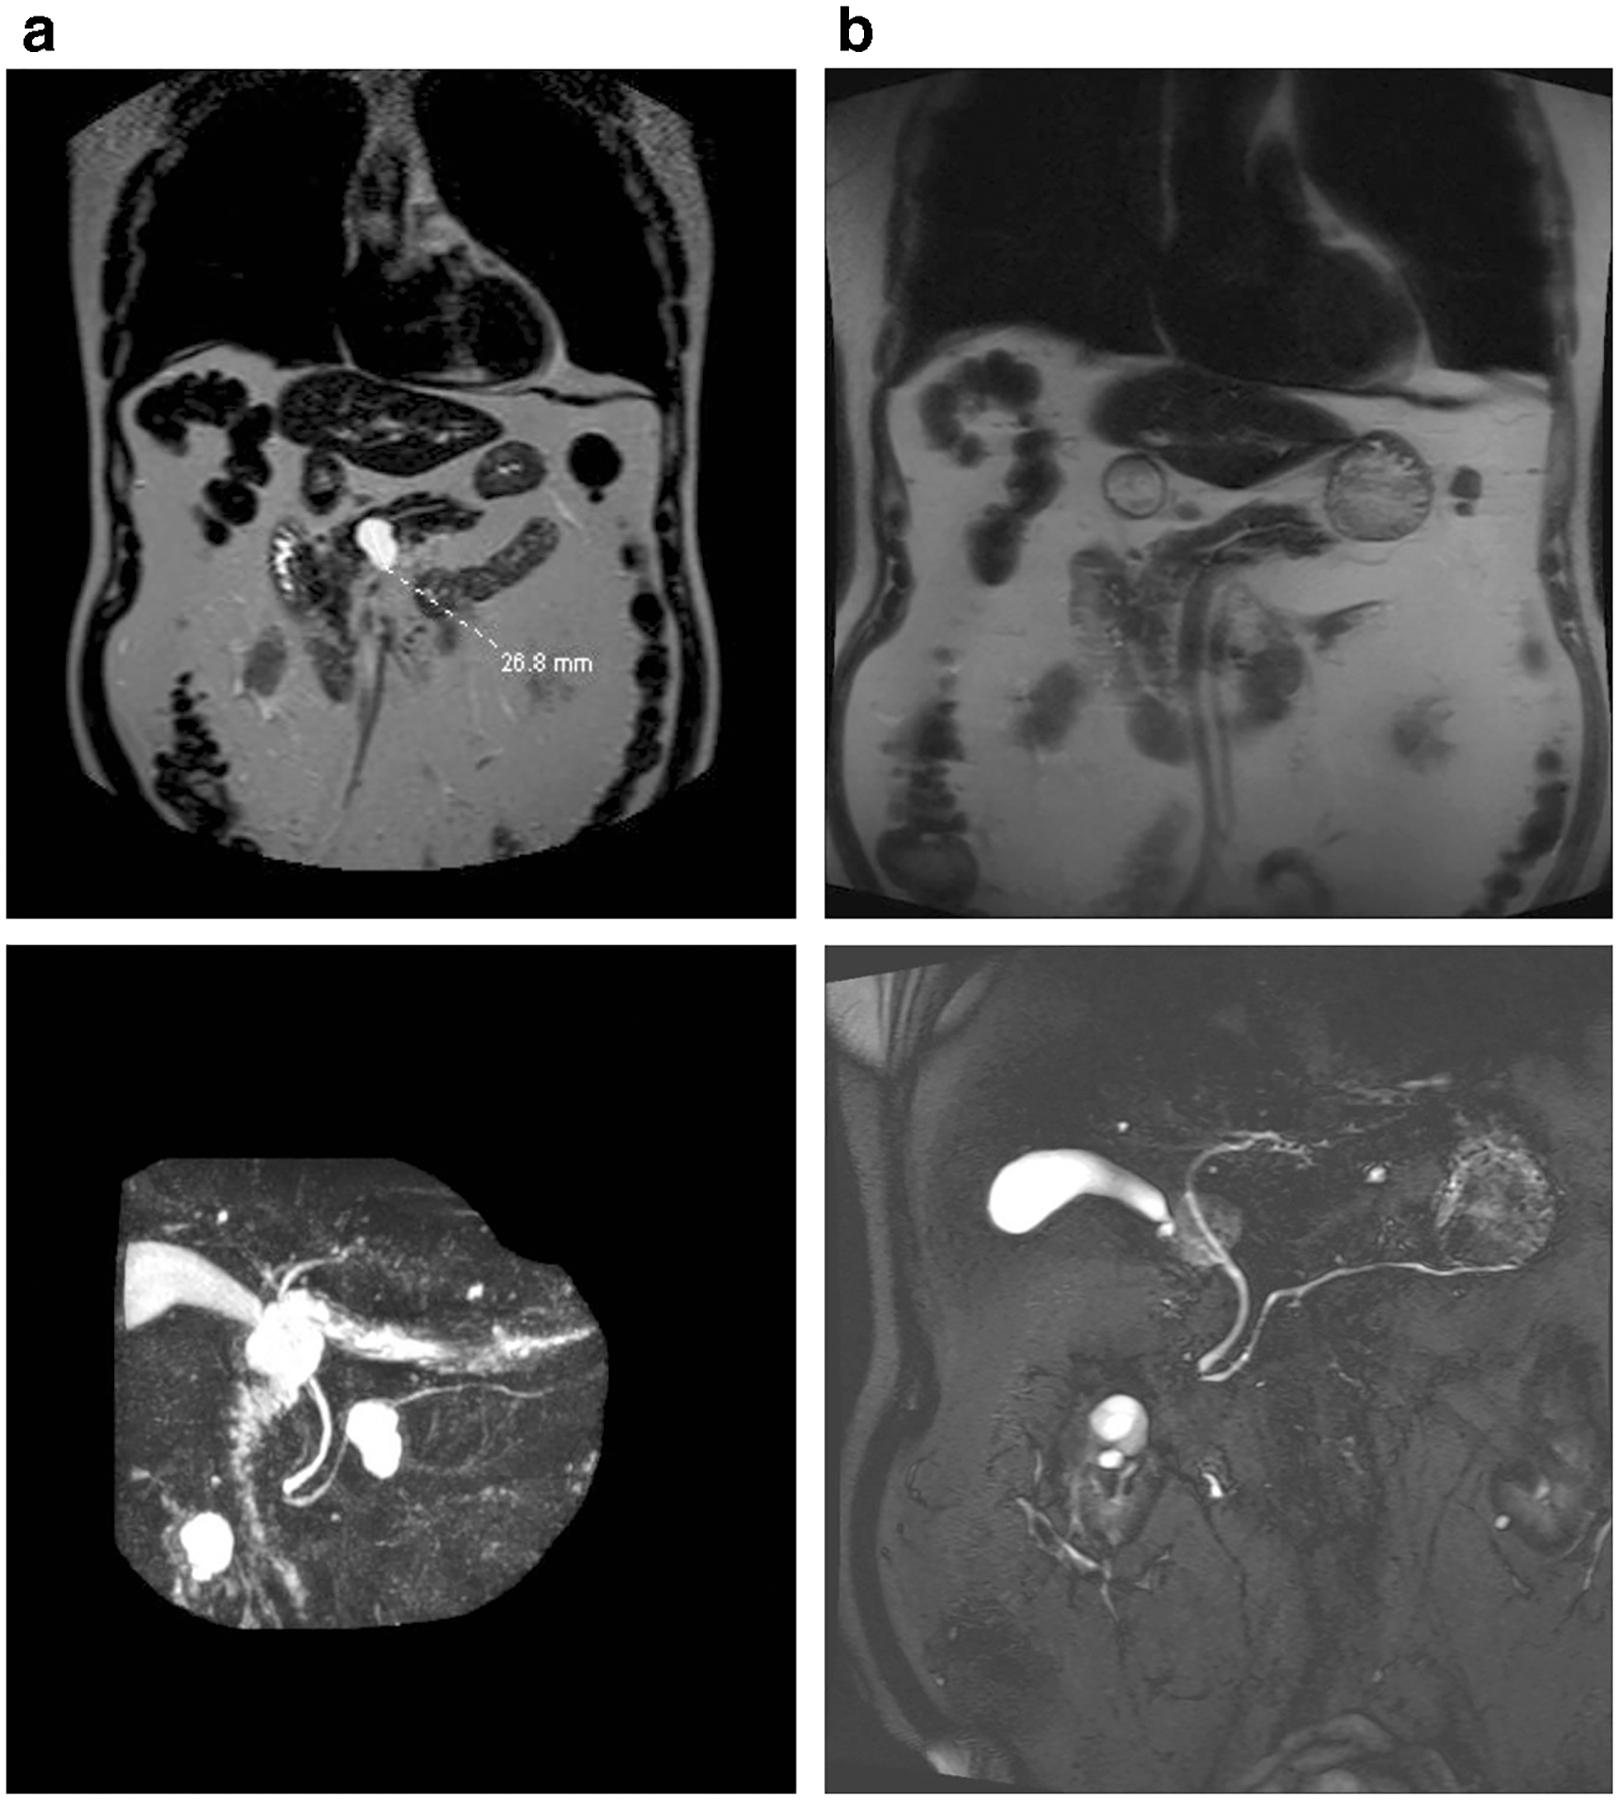

EUS-Guided Pancreatic Cyst Ablation: a Clinical and Technical Review.

Endoscopic ultrasound-guided chemoablation of pancreatic cysts has been performed in neoplastic cysts, with varying levels of efficacy. Safety concerns arose due to the risk of pancreatitis in alcohol-based treatments; however, the most recent data using a non-alcohol chemoablation cocktail suggests that ablation is effective without the need for alcohol, resulting in a significantly more favorable adverse event profile. Endoscopic ultrasound-guided chemoablation of neoplastic pancreatic cysts is a promising, minimally invasive approach for treatment of cysts, with recent significant advances in safety and efficacy, suggesting that it should play a role in the treatment algorithm.

已对肿瘤性囊肿进行了内镜超声引导下的胰腺囊肿化学消融,疗效各异。基于酒精的治疗存在胰腺炎风险,引发了对安全性的担忧;然而,使用非酒精化学消融合剂的最新数据表明,无需酒精即可实现有效消融,不良事件谱明显更有利。内镜超声引导下对肿瘤性胰腺囊肿进行化学消融是一种有前景的微创囊肿治疗方法,近期在安全性和疗效方面取得了重大进展,表明其应在治疗方案中发挥作用。